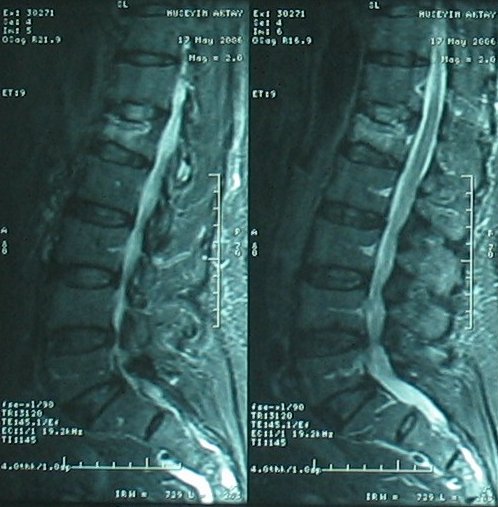

Kemik erimesine (osteoporoza) bağlı omurga kırığı olan hastada vertebroplasti (çimento ile dolgu) tedavisi